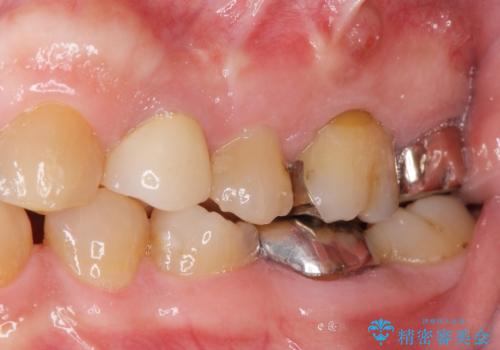

- 歯ぐき(ちょうど根の先のあたり)から膿が出て、根の治療を何度しても治らないことを主訴に来院された患者様です。

精査したところ、奥歯(左上67)の根尖部に位置した歯茎に瘻孔(膿の出口)ができており、CTを撮影し確認すると奥歯2本(左上67)の根尖病変は大きくつながっていました。

クラウンの種類:メタルボンドクラウン エコノミー